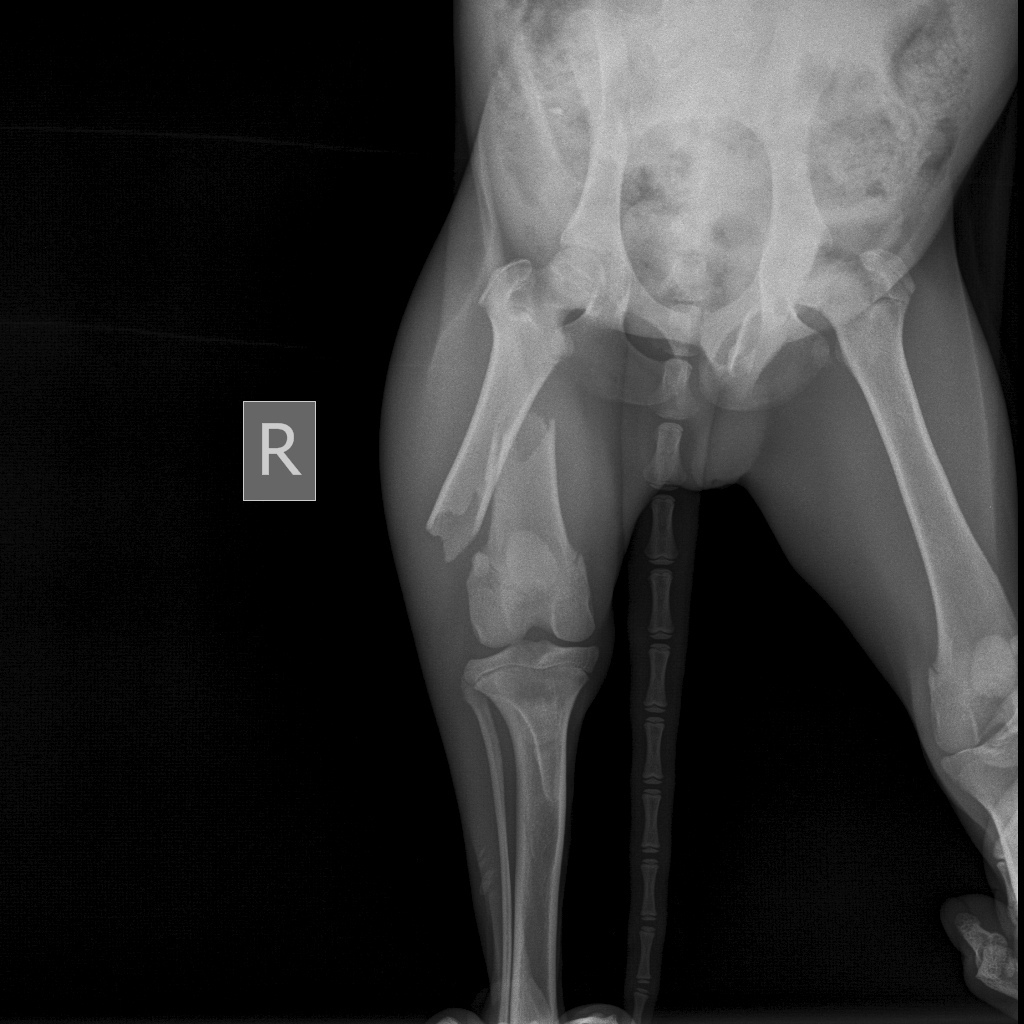

В клинике сообщили, что животное сильно истощено и со сломанным бедром. Возможно, его кто-то систематически избивал.